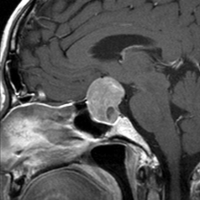

典型的なMRIの画像です

下垂体腺腫のMRIです。両側の視野障害(両耳側半盲)のために手術を受けた患者さんのものです。この腫瘍は非機能性腺腫といってホルモンを出さない腫瘍でした。少し大きめでしたが全部取れて視野の障害はよくなりました。

左の2枚はガドリニウム造影剤を使って写したもので腫瘍の形がよくわかります。右の1枚はT2強調画像と言います。MRIでは撮影の仕方によって見え方が違います。